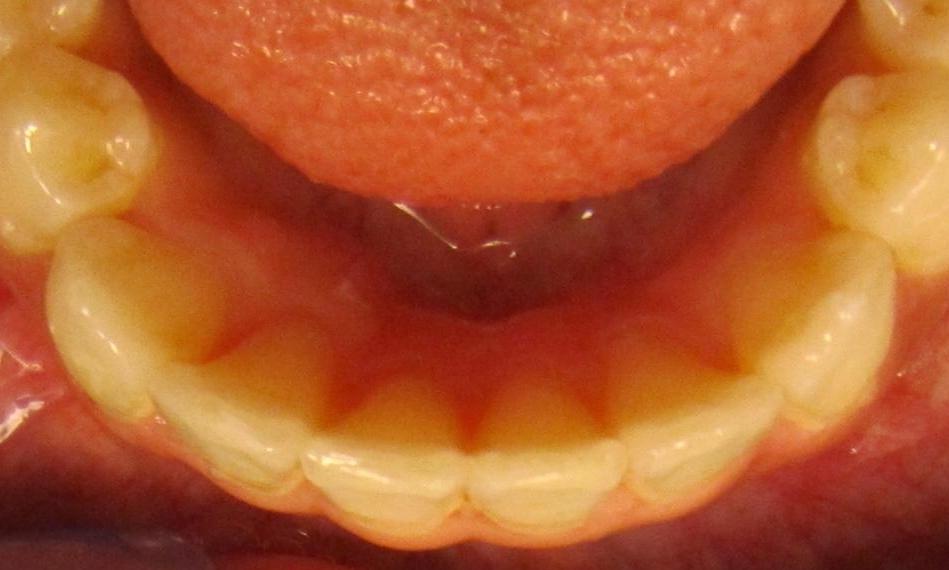

Invisalign was used to correct crowding on the lower teeth.

Before

After